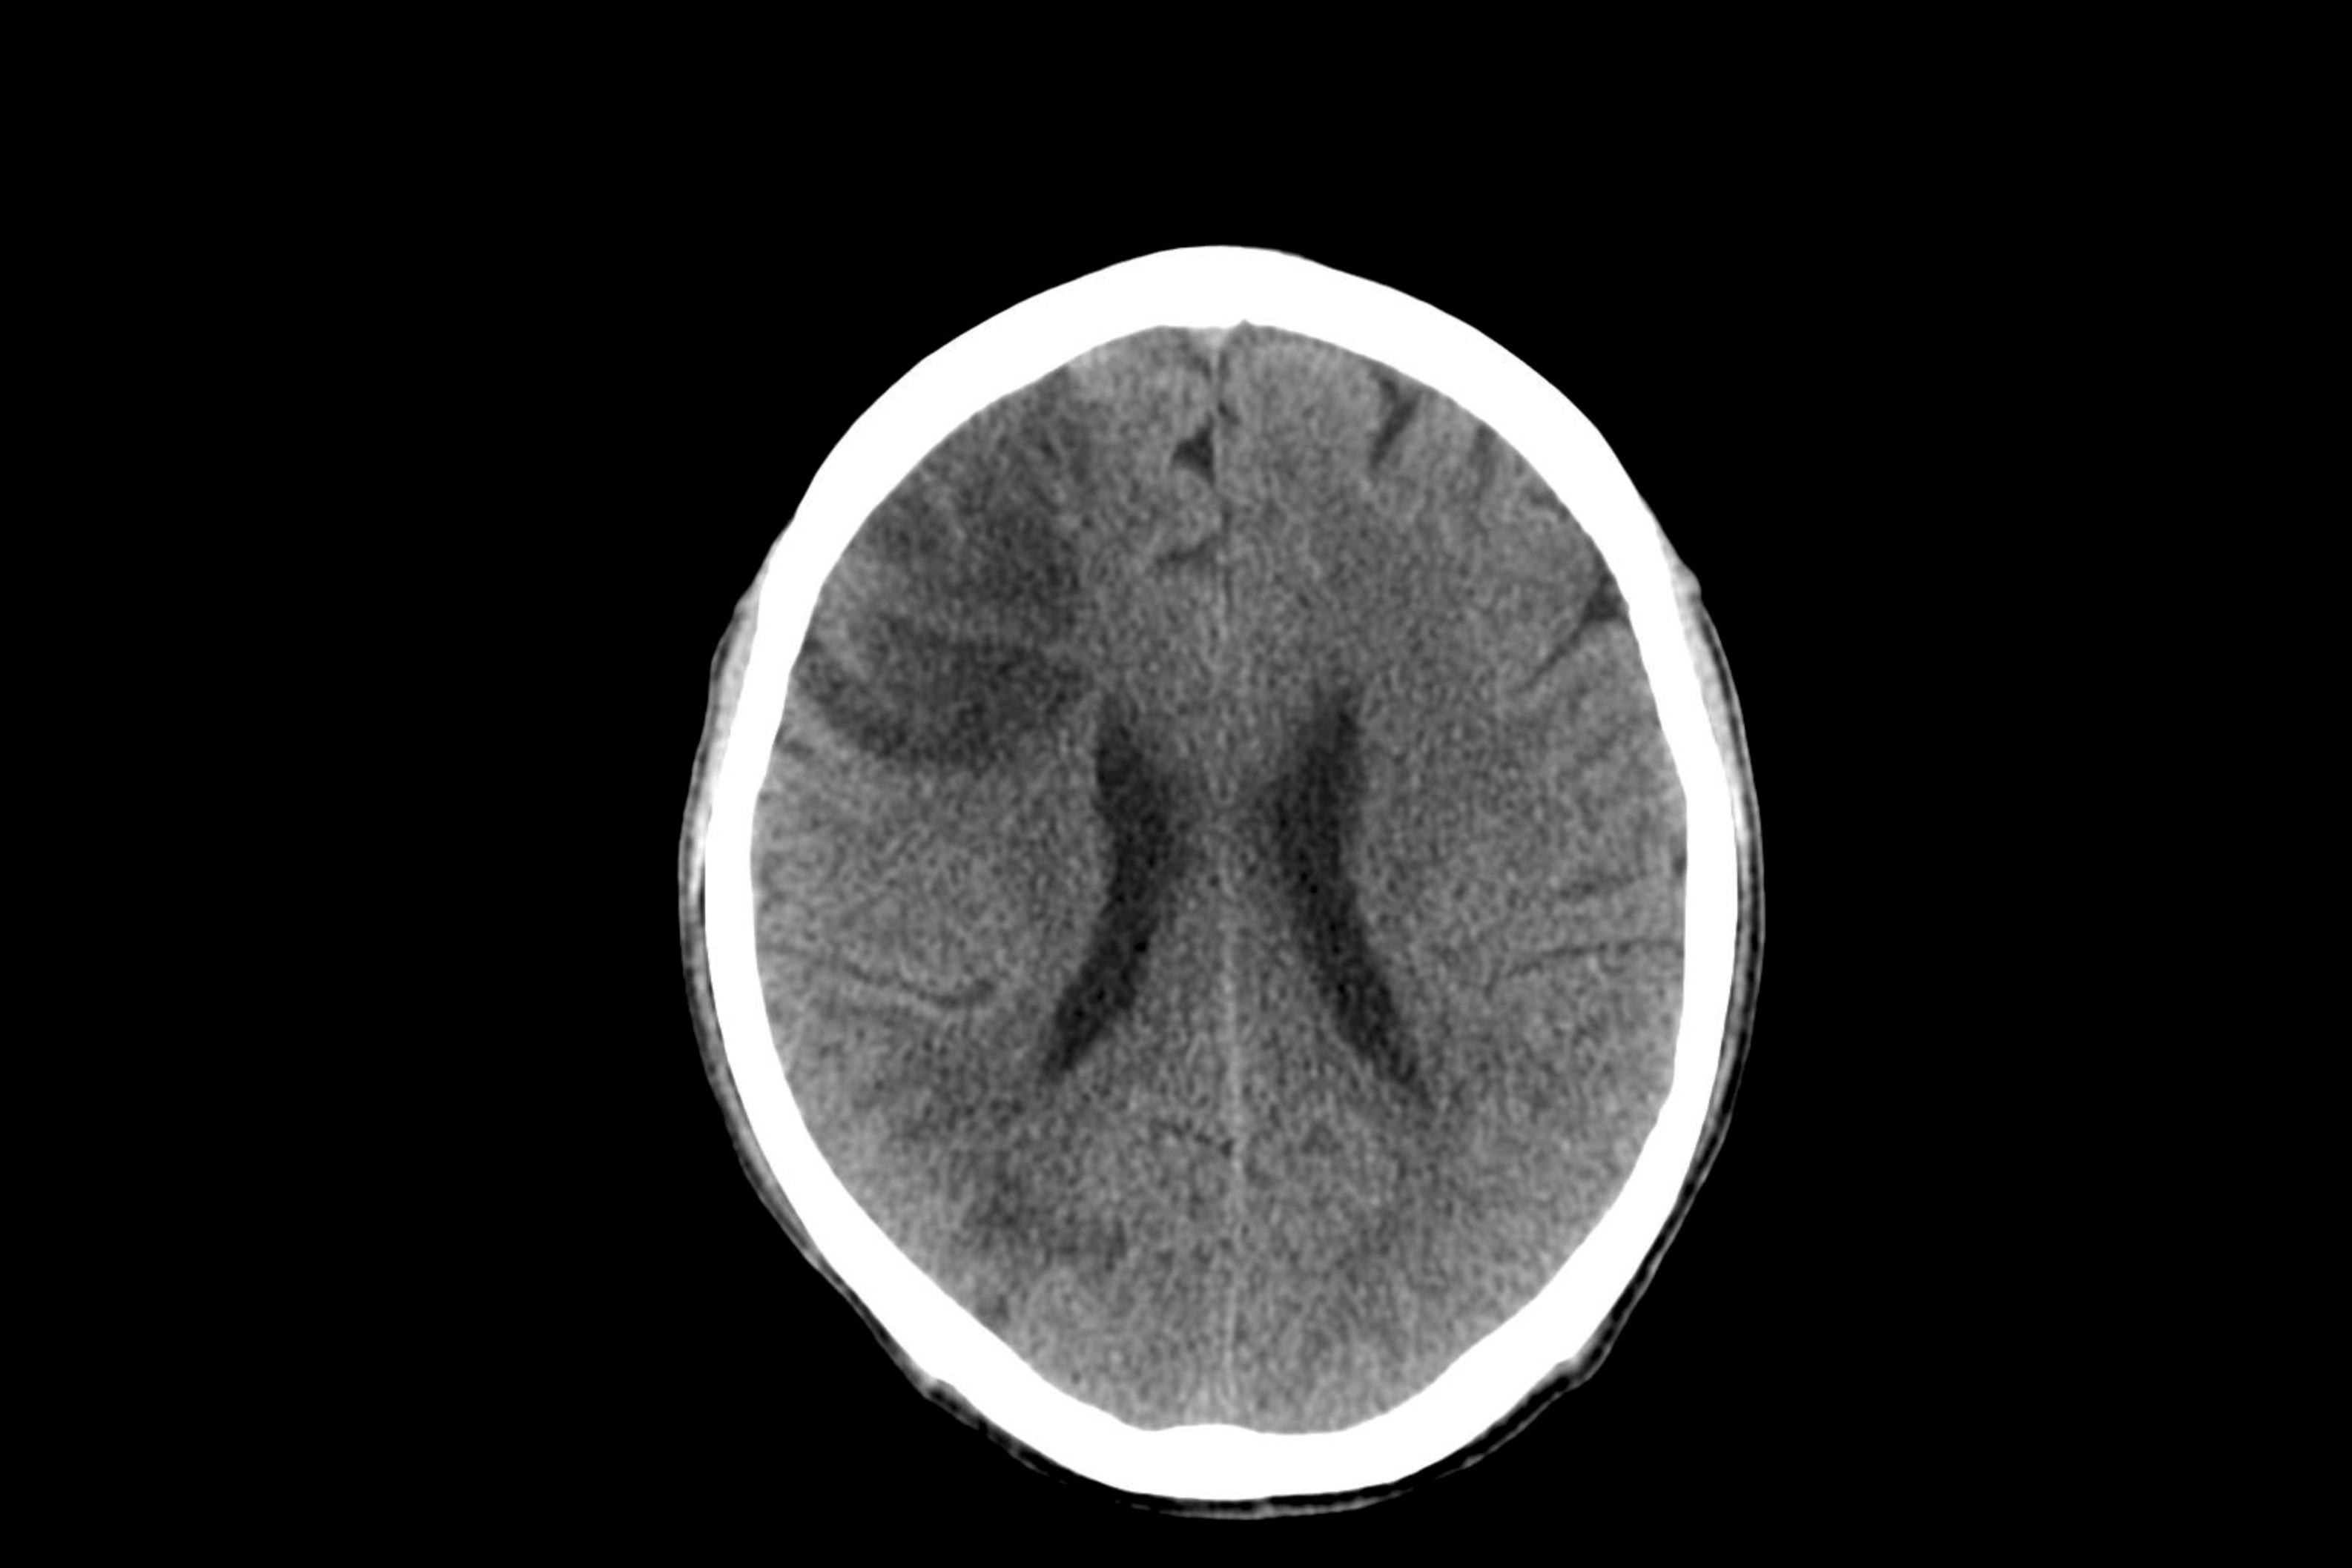

Radiologiske bilder og beskrivelse av disse er et viktig bidrag i dagens slagbehandling. Det er en svakhet at data i Norsk hjerneslagregister (NHR) inneholder svært begrenset informasjon om bilderesultater, og pr i dag finnes det ikke automatisert direkte datafangst mellom Norsk hjerneslagregister og pasientjournal. Dette medfører stor ressursbruk for innrapportering, til dels mangelfulle registreringer og redusert datakvalitet.

Dette ønsker prosjektet “Strukturert registrering av bildedata og journaldata for hjerneslagpasienter” å gjøre noe med. Prosjektet skal standardisere og strukturere data og etablere en infrastruktur for innsamling, lagring, bearbeiding og analyse av kliniske og bildediagnostiske data fra fortløpende innlagte slagpasienter med kobling til Norsk hjerneslagregister. Prosjektet vil utnytte allerede tilgjengelige KI- verktøy i eksisterende journalsystem til å hente ut nødvendige data fra fritekst i pasientjournal. Formålet er å forbedre kvaliteten på pasientbehandling, redusere arbeidsbelastning på helsepersonell og legge til rette for fremtidig kvalitetssikring og forskning.